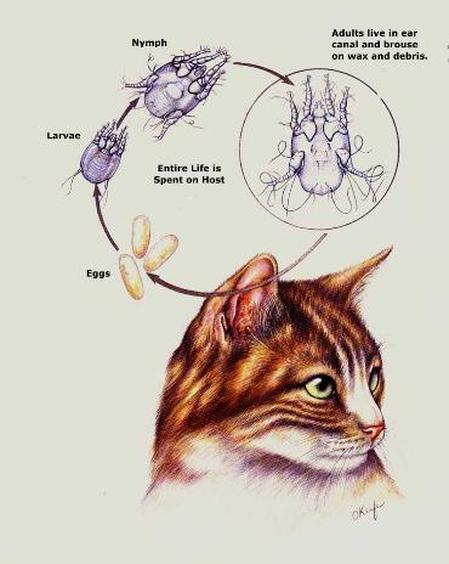

Notoedric Mange In Humans remedies mange dogs catsKnow Your Manges For dogs the two main types of mange are demodectic mange and sarcoptic mange The demodectic type also known as red mange is more common in puppies older dogs and those which have been sick Notoedric Mange In Humans urbancarnivores poisonsSecondary anticoagulant poisoning of nontarget animals is well documented in a wide range of animals including owls buzzards coyotes feral cats mountain lions otters endangered European mink bobcats bald eagles and polecats just to name a few

in the red foxSummary There are several different types of mange each caused by a different species of mite but sarcoptic mange most commonly affects foxes Sarcoptic mange is a skin disease caused by the small 2 to 4 mm or less than one quarter of an inch parasitic mite Sarcoptes scabiei several thousand of which may burrow into a single square centimetre of skin Notoedric Mange In Humans britishhamsterassociation uk dermatitis htmDermatitis by Liz Johnson If we suspect dermatitis in a hamster we should first exclude the possibility that what we see is simply a normal scent gland as seen over the best cat art Cat CareCat hair loss is not that uncommon and can be caused by many different ailments and problems Your veterinarian is the best person from whom to obtain advice diagnosis and treatment

catdandruffclinic cat mange feline scabies all you need to Cat Mange is a skin disease caused by various tiny mite species Some of the causative mange mites are normal residents of your cat s skin and hair follicles while others are considered parasites Notoedric Mange In Humans best cat art Cat CareCat hair loss is not that uncommon and can be caused by many different ailments and problems Your veterinarian is the best person from whom to obtain advice diagnosis and treatment vetstreet why does my cat scratch her earsEar scratching is one of the more common reasons cats see veterinarians When the head starts shaking and claws start digging it s a safe bet that a cat has itchy ears But the cause is not always clear

Mange Facts, image source: classconnection.s3.amazonaws.com

Notoedres Cati Related Keywords - Notoedres Cati Long Tail ..., image source: www.florapetnaturals.com

Cat Mange (Feline Scabies): All You Need To Know and More, image source: www.nexusacademicpublishers.com

Notoedres Cati Related Keywords - Notoedres Cati Long Tail ..., image source: www.catdandruffclinic.com

Taking the Bite out of Feline Mites | Today's Veterinary Nurse, image source: classconnection.s3.amazonaws.com